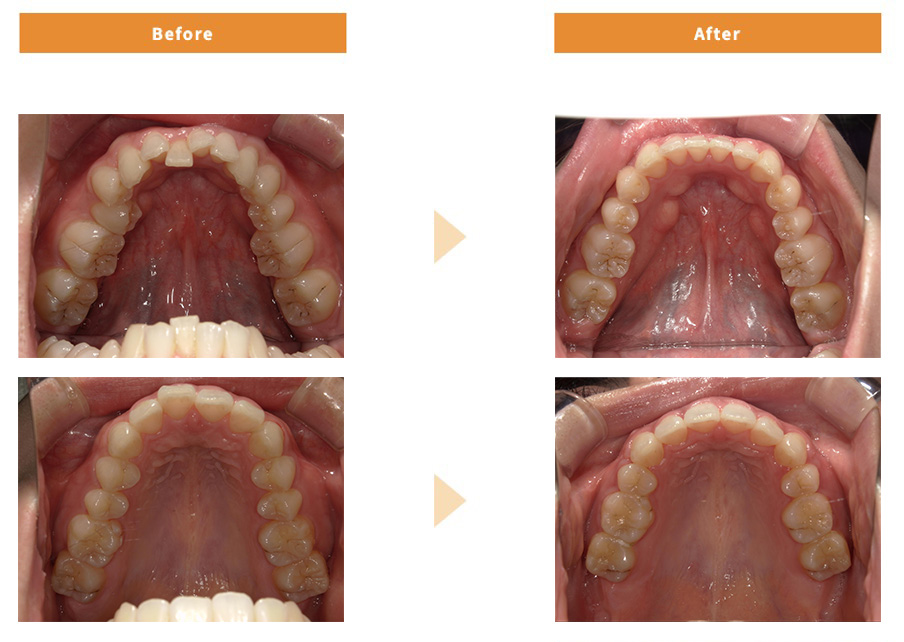

症例のご紹介

ワイヤー矯正

| 治療費用 | 849,200円 |

|---|---|

| 治療期間 | 1年半 |

| 患者様の主訴 | 叢生 |

| 治療内容 | ワイヤー矯正 |